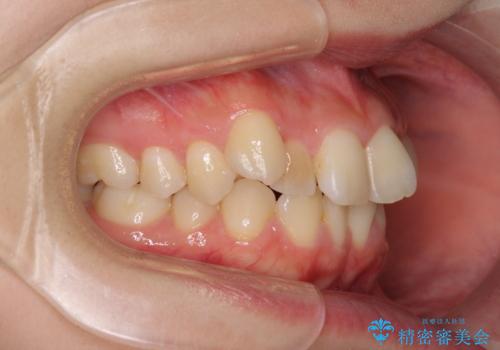

本人は気づいていませんでしたが、下顎前歯が2本欠損しており、上下の歯列がアンバランスとなりデコボコになっていました。

上下のバランスを取るため、上顎左右第一小臼歯2本を抜歯し、ワイヤー矯正を行うこととしました。